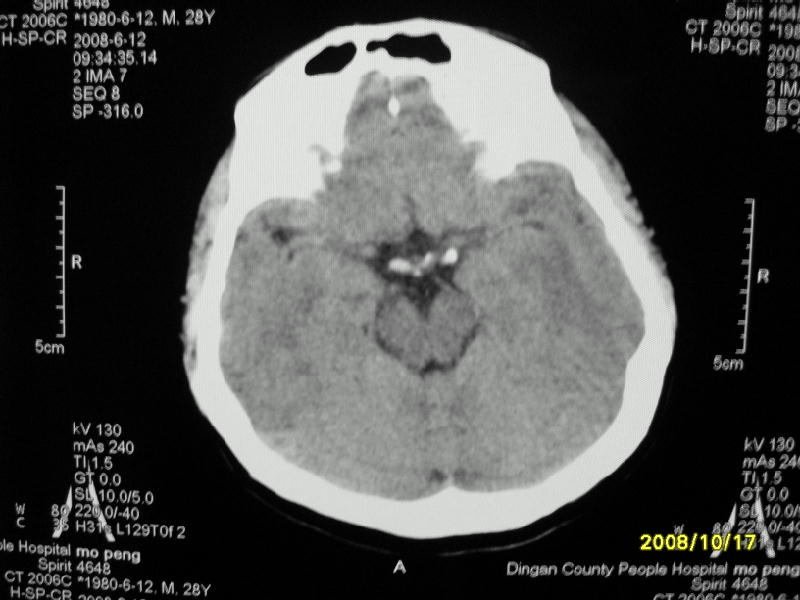

检查名称:     ct颅脑平扫           男     28岁

表现:左顶叶见斑点状致密影。边缘清,大小约0。3*1。0cm,余脑实质密度及灰白质结构示见异常。脑室系统大小,形态,密度未见异常。脑沟。脑裂。脑池未见异常密度影。中线结构无移位。

印象:左顶叶少许钙化灶

左顶叶见斑点状致密影。边缘清,大小约0。3*1。0cm,余脑实质密度及灰白质结构示见异常。脑室系统大小,形态,密度未见异常。脑沟。脑裂。脑池未见异常密度影。中线结构无移位。

印象:左顶叶少许钙化灶。

镰旁钙化

考虑脑膜钙化或脑膜血管钙化

镰旁钙化或顶骨内板骨嵴部分容积效应,建议mri矢状位扫描观察与顶骨的关系。排外后者。

左顶叶见斑点状致密影